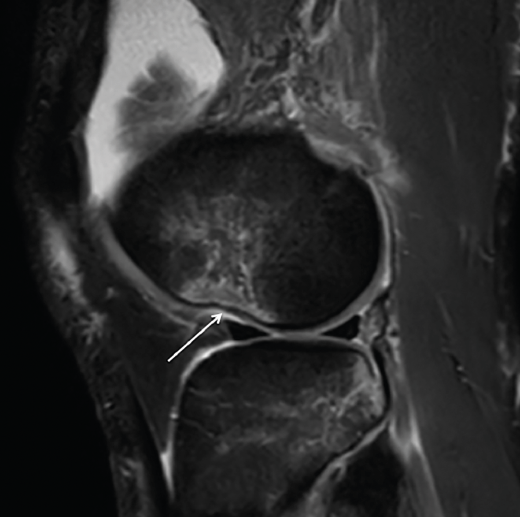

Se ha demostrado la correlación entre los hallazgos en ecografía y RM con alto grado de pivot shift en lesiones de LAL(36,40). Mediante esta exploración pueden detectarse tanto la lesión propiamente dicha del LAL, como la fractura de Segond y otros signos indirectos como la impactación del cóndilo femoral lateral (Figura 3).

Figura 3. Imagen sagital de resonancia magnética del cóndilo femoral externo en la que puede apreciarse el signo de impactación (nocht sign, flecha blanca). Puede interpretarse como signo indirecto de afectación del ligamento anterolateral .